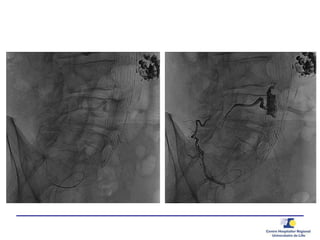

Guide de pression 0.014’’

20 G needle0.014’’ PressureWire

 Pression

Aorta

Sac